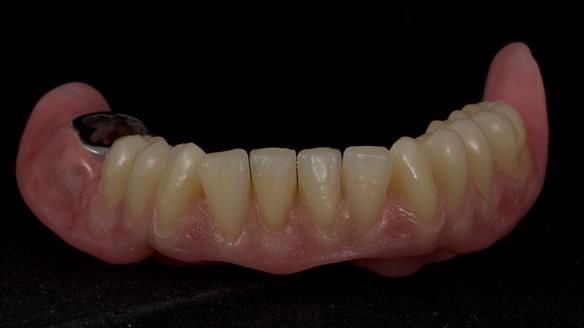

However, once Rowan and I reviewed the remaining metal crown on tooth 46, we realised it would make an ideal abutment for a gasket denture. By reshaping the lingual surface of the crown, we created an excellent gasket seal.

This approach worked far better than the proposed ring-clasp design - improving retention, comfort, and aesthetics while keeping the design clean and simple.

For both the upper and lower dentures, we used Schottlander Enigma Life teeth. I’ve been using these since 2014 and they’ve been outstanding - the surface texture, colour depth, and light reflection are superb. When arranged to mirror the patient’s natural tooth positions, they look completely lifelike.

- The gasket seal around 46 was made using retention.sil 200, producing a precise, cushioned fit.

- Enigma Life teeth provided a natural, individualised appearance perfectly matching Mary’s desired smile.